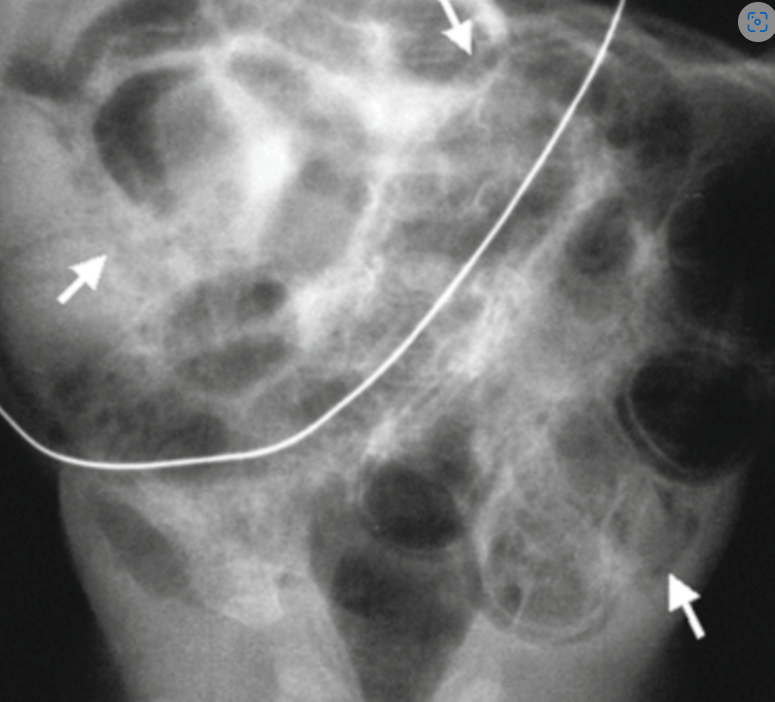

NEC